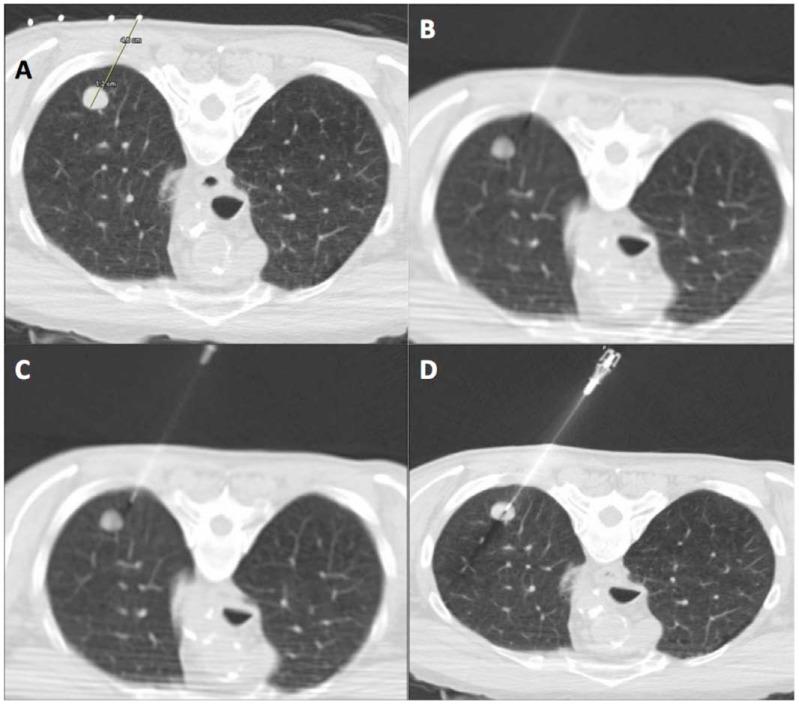

Percutanous needle biopsy of the lung (PNBL), under image guidance, has established itself as a safe and effective minimally-invasive method of obtaining a tissue diagnosis of pulmonary lesions, for selected patients with suspected pathologic processes. The purpose of this study was to evaluate the diagnostic yield and safety of percutaneous core biopsy of the lung (PCBL) without Fine Needle Aspiration Biopsy (FNAB), with specific attention to potential risk factors that may predict post-biopsy pneumothorax.

A retrospective analysis of 75 consecutive PCBL procedures between January 2006 to March 2008 involving 72 patients with a documented pulmonary nodule or mass lesion on CT scan of Thorax. The study population included 38 males (52.8%) and 34 females (47.2%) aged 20-85 years (mean age 63.6 years). A co-axial cutting system with a 19-gauge outer needle and a 20-gauge inner automated cutting needle (Temno, Allegiance Healthcare Corporation, Ohio, USA) was used in all patients.

Lesions varied in size from 0.7cm to 10.7cm (mean maximum trans-axial diameter 3.1cm). The mean number of core biopsy samples obtained was 3.1 (range 1-5). Of the 75 PCBL procedures, 71 yielded specimens adequate for histopathologic evaluation, consistent with a technical success rate of 95%. Malignancy was detected in 48 specimens (64%) and benign diagnoses were identified in 23 specimens (31%). As mentioned, 4 specimens (5%) were nondiagnostic. The most common biopsy-induced complication was pneumothorax, occurring in 15 patients (20%), with 4 (5.3%) requiring thoracostomy tube placement.

在影像引导下,经皮肺穿刺活检(PNBL)已成为一种安全有效的微创方法,可为选定的疑似病理过程患者获取肺部病变的组织诊断。本研究的目的是评估不进行细针穿刺抽吸活检(FNAB)的经皮肺芯针活检(PCBL)的诊断率和安全性,特别关注可能预测活检后气胸的潜在危险因素。

对2006年1月至2008年3月期间连续进行的75例PCBL手术进行回顾性分析,这些手术涉及72例经胸部CT扫描记录有肺结节或肿块病变的患者。研究人群包括38名男性(52.8%)和34名女性(47.2%),年龄在20 - 85岁之间(平均年龄63.6岁)。所有患者均使用带有19号外针和20号内自动切割针的同轴切割系统(Temno,美国俄亥俄州忠诚医疗保健公司)。

病变大小从0.7厘米至10.7厘米不等(平均最大横轴直径3.1厘米)。获得的芯针活检样本平均数量为3.1个(范围为1 - 5个)。在75例PCBL手术中,71例获得了足以进行组织病理学评估的标本,技术成功率为95%。48例标本(64%)检测到恶性肿瘤,23例标本(31%)确定为良性诊断。如前所述,4例标本(5%)无法诊断。最常见的活检引起的并发症是气胸,15例患者(20%)发生气胸,其中4例(5.3%)需要放置胸腔引流管。